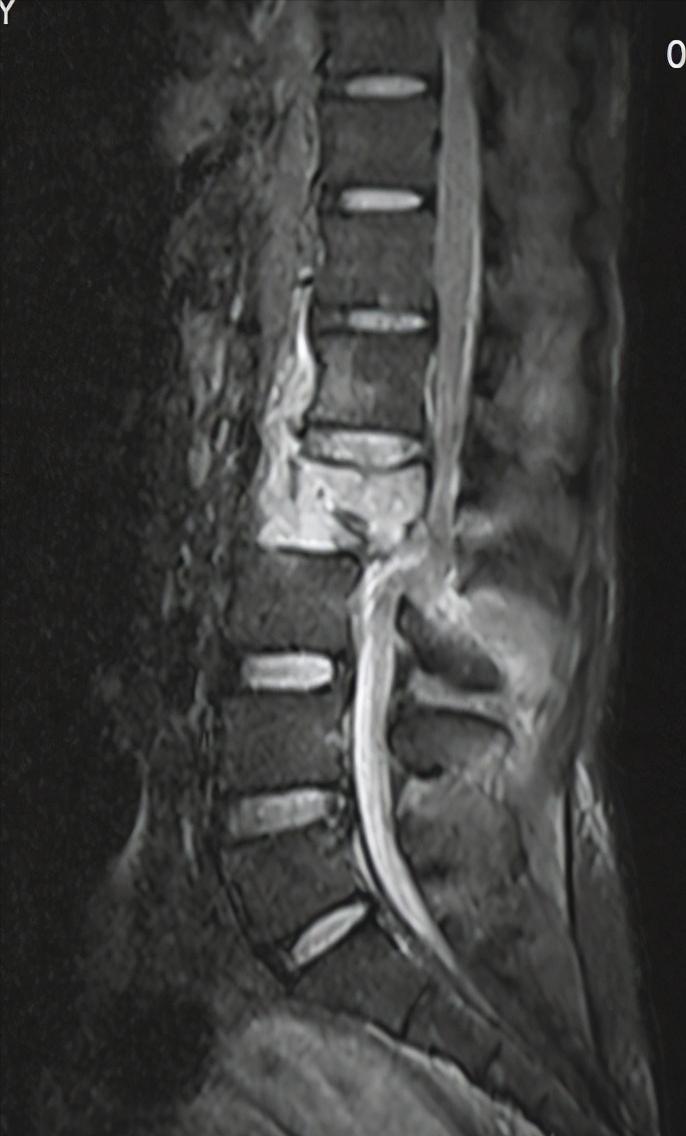

诊断为:1、 腰2椎体爆裂性骨折伴截瘫

腰椎MR见脊髓明显卡压